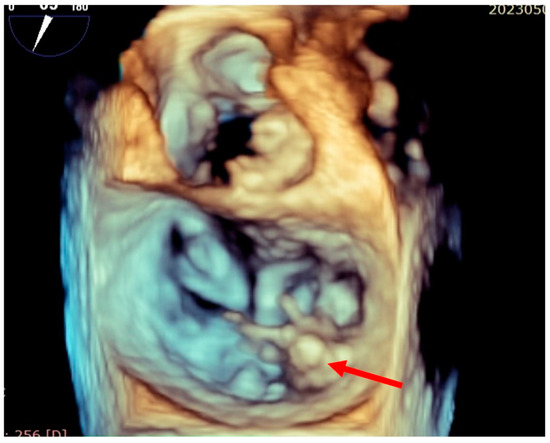

| Preoperative findings | The patient was referred for progressively worsening dyspnea and fatigue and diagnosed with severe mitral regurgitation. Transthoracic echocardiography revealed severe mitral regurgitations caused by posterior leaflet prolapse and flail due to chordae rupture. | |